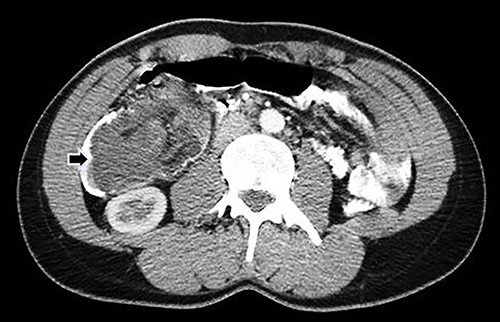

Computed tomography (CT) of the abdomen and pelvis with oral and intravenous contrast was performed (Fig. 1), and emergency surgery was decided due to the suspected ileocolic intussusception with a probable tumor origin (Fig. 2). The preoperative diagnoses were malignant cecum tumor (adenocarcinoma, sarcoma) or benign tumor (lipoma, villous tumor).

Abdominal CT with oral and IV contrast, coronal view; tumoral mass and intussusception (arrow).